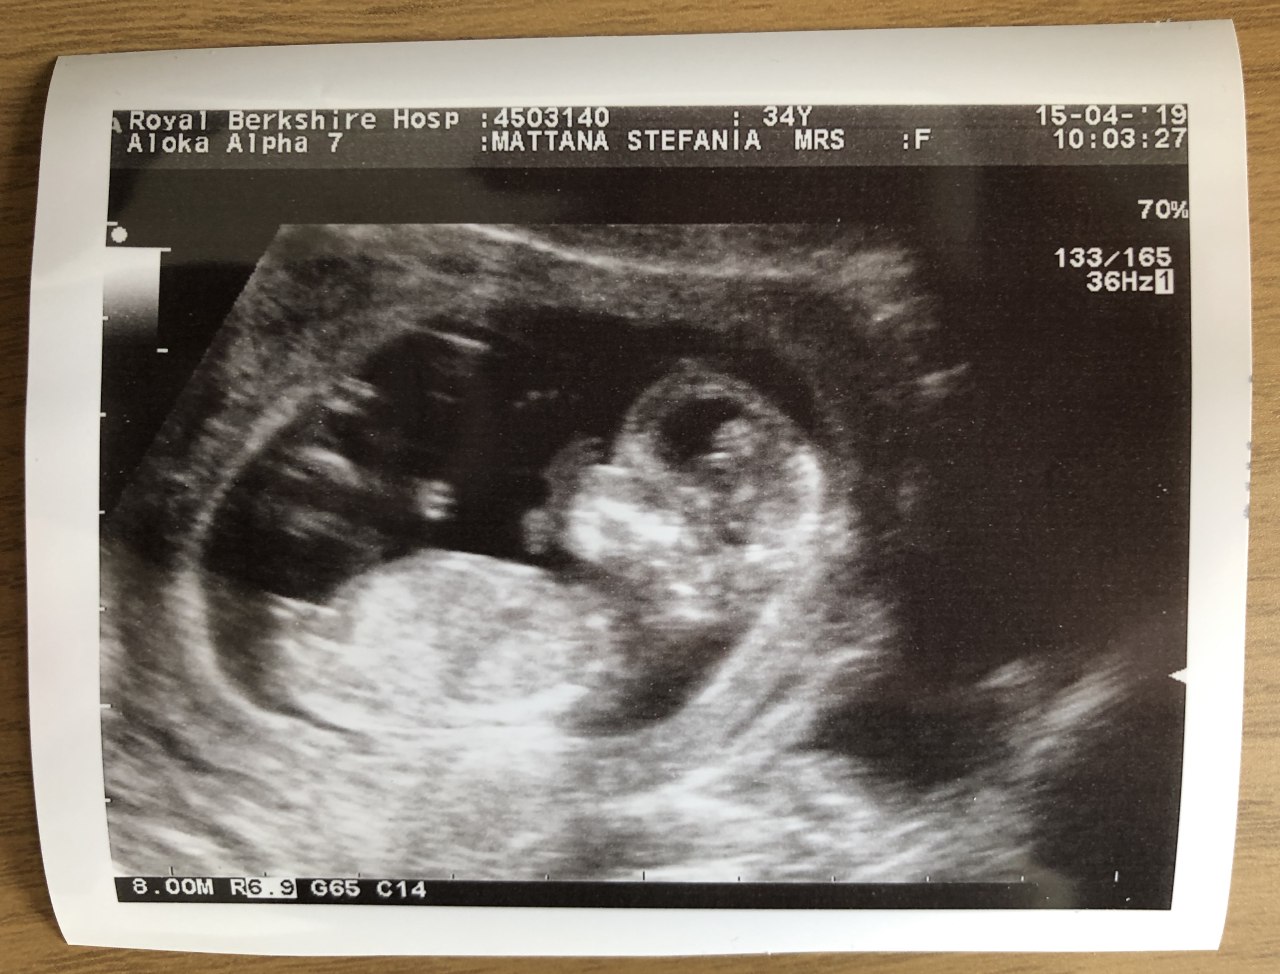

Frosty stretching one arm

At some point the sonographer got also a little upset as she couldn’t take the proper measurements properly! Because of all this fetal activity, it wasn’t possible to hear the heartbeat – it’d be too complicated to catch the heart well enough to trigger the heartbeat-sound magic. ¯_(ツ)_/¯

We got content with another sonographer’s magic resulting in a third picture:

If you look at it closely, you can see Frosty’s heart: two chambers are very clearly visible!